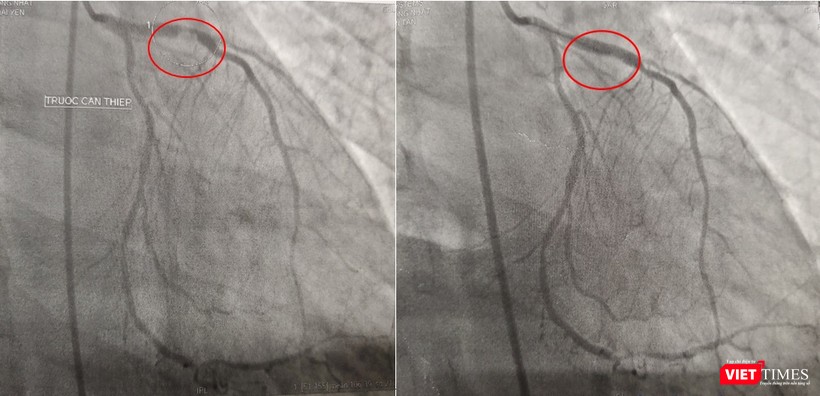

| Kết quả chụp DSA mạch vành: bán tắc đoạn gần LAD do huyết khối, can thiệp và đặt stent cho bệnh nhân |

Kết quả chụp mạch máu tại phòng DSA cho thấy bệnh nhân bị đột quỵ não do huyết khối gây ra tắc hoàn toàn một nhánh động mạch lớn của não, đồng thời, còn phát bệnh nhân bị bệnh cả 3 nhánh động mạch vành nặng với huyết khối gây tắc gần hoàn nhánh động mạch lớn nuôi trái tim LAD (nhánh động mạch liên thất trước), 2 nhánh còn lại có một nhánh hẹp nặng, một nhánh bị tắc hoàn toàn mạn tính đã lâu.